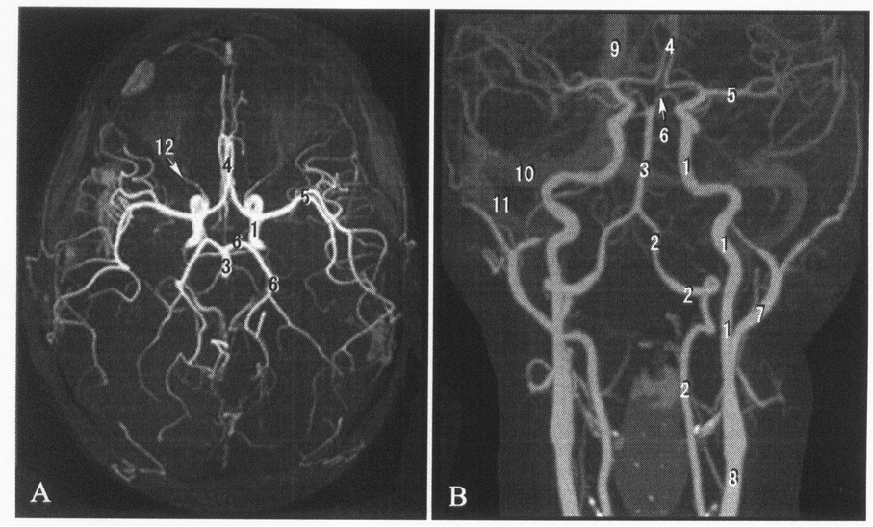

1 头部X线作业